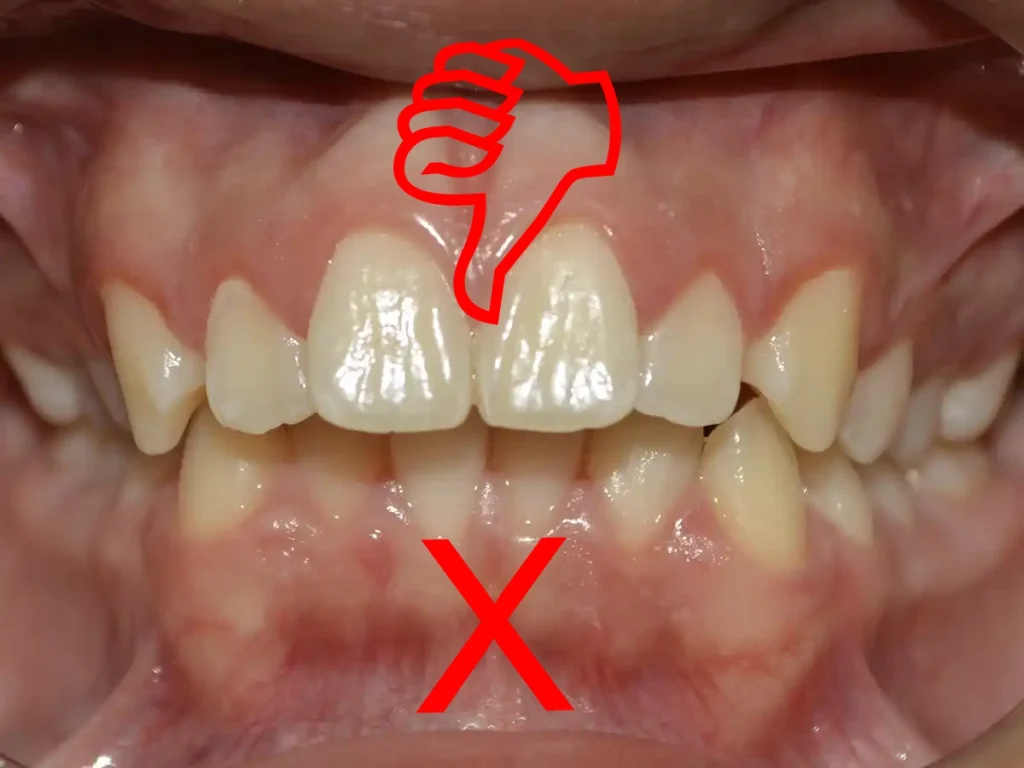

En pacientes infantiles, no conviene esperar a que salgan todos los dientes para decidir. Lo más importante es diagnosticar a tiempo si el crecimiento, el espacio disponible y la relación entre las arcadas necesitan ser guiados tempranamente.

La observación clínica, junto con el estudio de modelos, fotografías y cefalometría, permitió analizar la posición dentaria, la relación esqueletal y el espacio disponible. Esto permitió definir que era oportuno intervenir en esta etapa.

Recuerda: se ve bien a los siete, pero NO a los diecisiete.